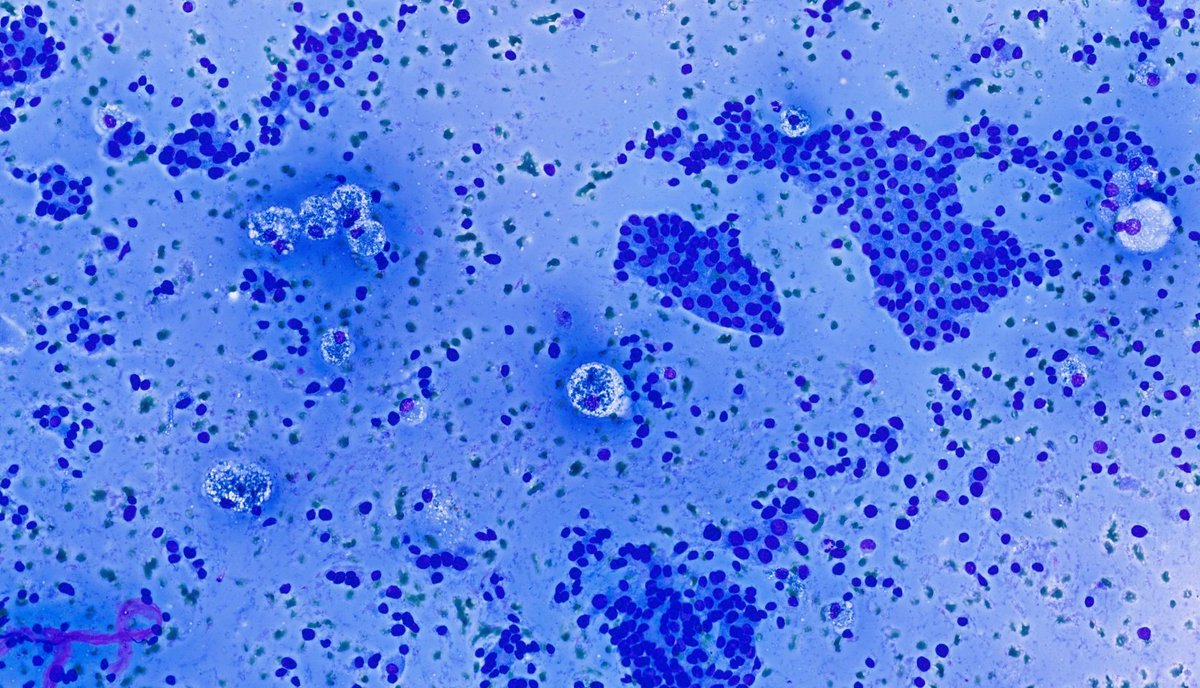

FNA from a 45yo man with a history of pheochromocytoma, what is your interpretation? A) Papillary thyroid carcinoma B) Follicular Neoplasm C) Medullary thyroid carcinoma D) Metastatic pheochromocytoma #CytoPath #EndoPath #PathTwitter #Pathology

A) Papillary thyroid carcinoma

B) Follicular Neoplasm

C) Medullary thyroid carcinoma

D) Metastatic pheochromocytoma